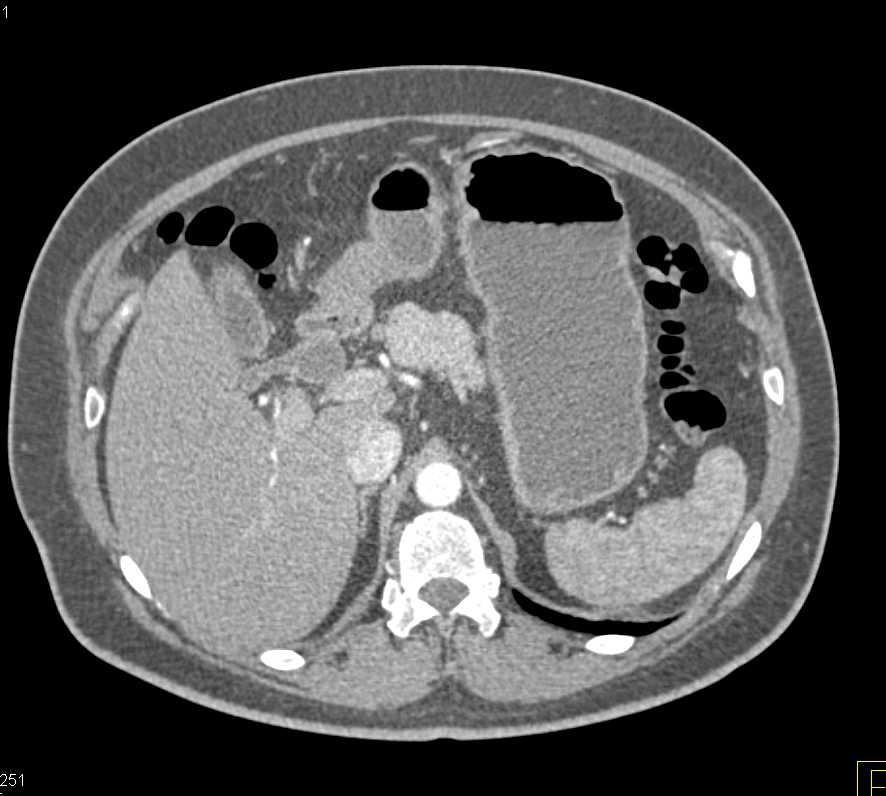

Professors Satomi Kawamoto and Professor Elliot K. Fishman (@ctisus), Associate Professor @LindaChuMD (@LindaChuMD), and Research Fellows Mohammad Yasrab and Juan Felipe Lopez-Ramirez (@FelipeLopezMD), presented an educational exhibit on βThe Challenges in the Detection and